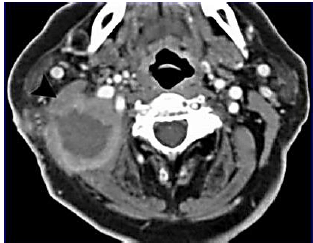

Paciente, sexo masculino, 22 anos, em tratamento para otite média aguda, há 7 dias retornou ao pronto-socorro por manutenção de febre e otalgia, além de inchaço retroautricular e cervicalgia à direita. Ao exame físico: regular estado geral; febril (39° C); e, abaulamento e hiperemia retroauricular dolorosa à direita com extensão inferior para região cervical com deslocamento anterior de pavilhão auricular ipsilateral. Presença de rigidez à movimentação cervical; ausência de sinais de Kernig e Brudzinski. Otoscopia: membrana timpânica íntegra à esquerda e conduto auditivo externo abaulado e hiperemiado. Realizada tomografia:

O diagnóstico da complicação evidenciada na imagem e a melhor conduta são, respectivamente: